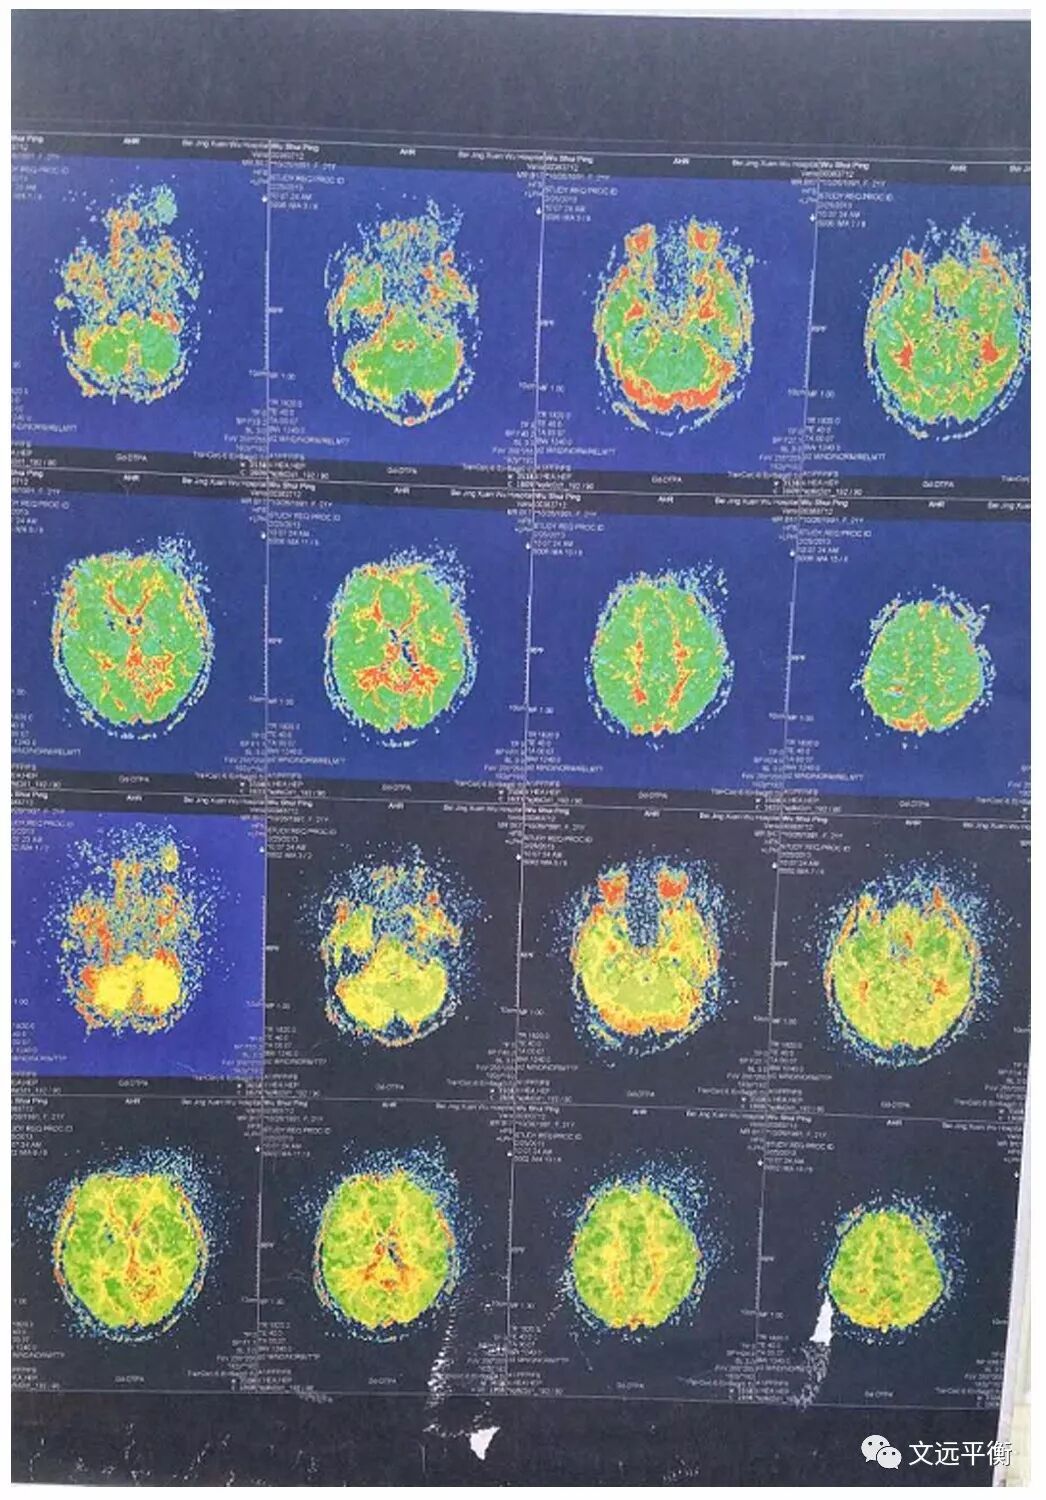

影像资料对比:图一、二。MRI平扫+增强+灌注扫描(2013.2.25宣武医院)报告提示:脑内多发异常信号,梗死伴渗血?血管炎?右侧乳突炎)

图四、五:复查颅脑MRI(2016.7.13龙岩市第二医院)提示:右侧基底节区,左枕叶.右侧额叶多发软化灶并周围胶纸增生,右侧额骨术后改变?